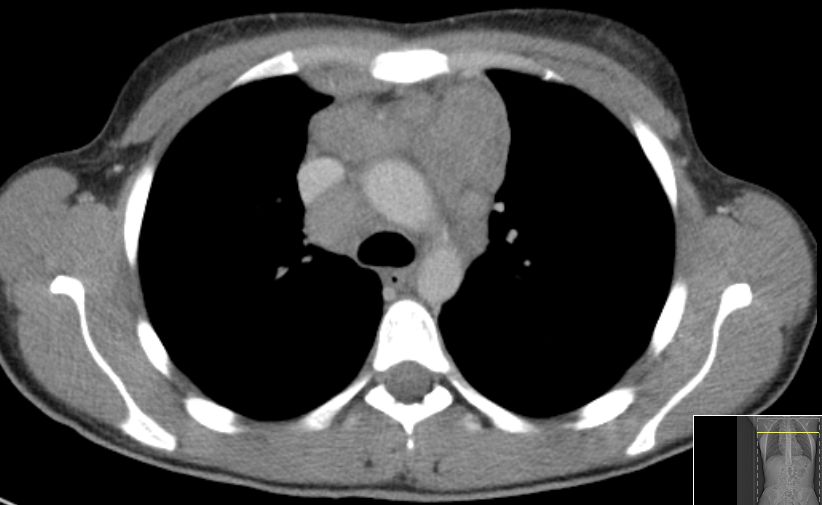

| thorakal | 21-jährige Frau mit Morbus Hodgkin mediastinal und zervikal beiderseits. Stadium IIA, Risikofaktor: hohe BSG. Noduläre Sklerose. | ||

![]() |